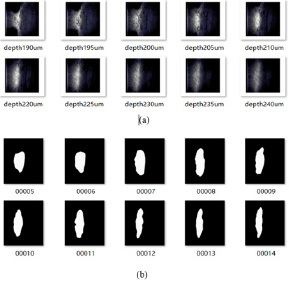

This paper builds a segmentation model of trabecular meshwork on the basis of U-Net network, and realizes the segmentation of trabecular meshwork image through pixel-by-pixel classification of the image. Due to the simpler and more intuitive advantages of keras to build a model, the unet model implemented here can not only deal with dichotomous problems, but also multi-class segmentation problems. The partial results of image segmentation of trabecular meshwork are shown in Figure 2. At present, there are many risks in the treatment of glaucoma, so it is urgent to find new methods to restore or replace the damaged trabecular meshwork. Therefore, it is very important to study the structure of trabecular meshwork. The image segmentation method based on deep learning was used to further study and analyze the trabecular meshwork, which laid a morphological foundation for the subsequent research on clinical diagnosis. The default parameter optimization model of Adam algorithm is used in the research. The initial learning rate of the model is 0.001, and the learning rate is dynamically adjusted during the training process. The batch size batch is set to 6. During the training process, the validation set loss passes through 119 steps, 42 epochs no longer decline and stop. The IoU(Intersection over Union), Dice coefficients, cross-entropy loss curve and acc change curve obtained from the Tensorboard visualization training process are shown in Figure 3, As shown in Figure 3, the light-colored lines in the figure are the original data curves, and the dark lines are the smoothed curves. The performance indicators used for image segmentation are IoU and Dice Coefficient. IoU is an index used to evaluate segmentation performance. The calculation method is: IoU = overlapping part/(real label + actual segmentation result).

The Dice Coefficient is used to evaluate the similarity between the segmentation result and the real label. Dice Coefficient = 2*predicted correct result/(predicted result + actual result). From Figure 2d, after 119 steps (42 epochs), the IoU is 0.8086, the accuracy acc is 0.9977, and the loss and dice coefficients are 0.101 and 0.8976, respectively, indicating that the model segmentation accuracy is more accurate and the training effect is better 3.3 Porosity of trabecular meshwork. When the TM inner layer was set at 0 μm, the porosity of the TM decreased with its increasing depth (in the flow direction). As shown in Figure 4a, the porosity of the TM with normal IOP was slowly decreased. While under the condition of elevated IOP Figure 4b, it was descending quickly. Additionally, the porosity of the TM in rat eyes with high IOP was less than that in the normal IOP group from the depth of 30 μm to the depth of 60 μm. Under the condition of elevated IOP (7.98 kPa), the porosity of the TM in the superficial region of the TM was rapidly decreasing from 0.65 to 0.31 and decreased from 0.31 (depth 30 μm) to 0.05 (depth 40 μm) in the deeper TM tissue adjacent to the SC. The TM tissue in the high IOP group exhibited the structures of compressed collagen fibres, and the total thickness of the TM decreased compared with the controls. It is indicated that the TM tissue can be collapsed by fusing into surrounding tissues due to the function of elevated IOP. In addition, the findings demonstrated that the changes in the TM tissue in pressurized eyes are large enough to lead to the increased outflow resistance.